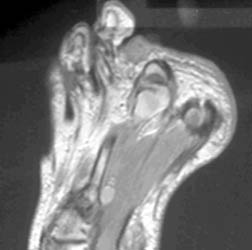

Metastatic Malignant Melanoma

Malignant melanoma develops from melanocytes derived from neural crest cells, usually occurring in the skin. Other primary sites include the scalp, oral and anogenital mucosal surfaces, nail beds, conjunctivae, orbit, esophagus, and leptomeninges. Metastases occur after a latent period of 2 to 20 years in lymph nodes, bone, lung, liver, spleen , GI tract, kidneys, adrenals, and subcutaneous tissue. Nonhemorrhagic melanotic metastases have high signal on T1 and intermediate to low signal on T2 W images, caused by intrinsic paramagnetic effects. These may be due to paramagnetic cations, free radicals, or an inherent characteristic of melanin. However, amelanotic melanoma without hemorrhage may have low signal on T1 and high signal on T2W images.

63-year-old male with a 1.2 x 0.9 cm mass in the plantar soft tissues between the 2nd and 3rd proximal phalanges. This mass has high signal on T1, intermediate signal on proton density, and low signal on T2 W images, consistent with melanotic metastatic melanoma.